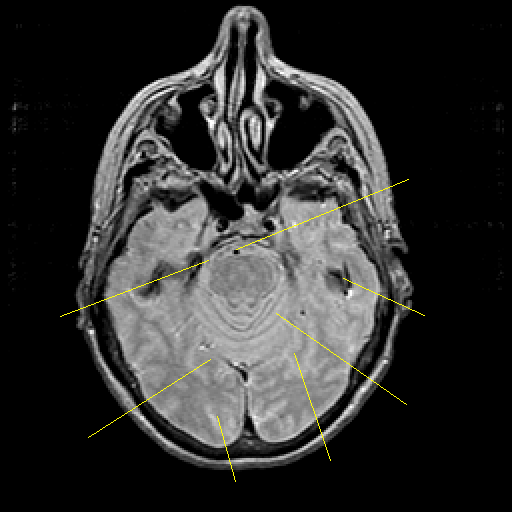

Proton density-weighted structural MR: Slice 17

Slice 17

Unlabeled

Pointers

Labeled